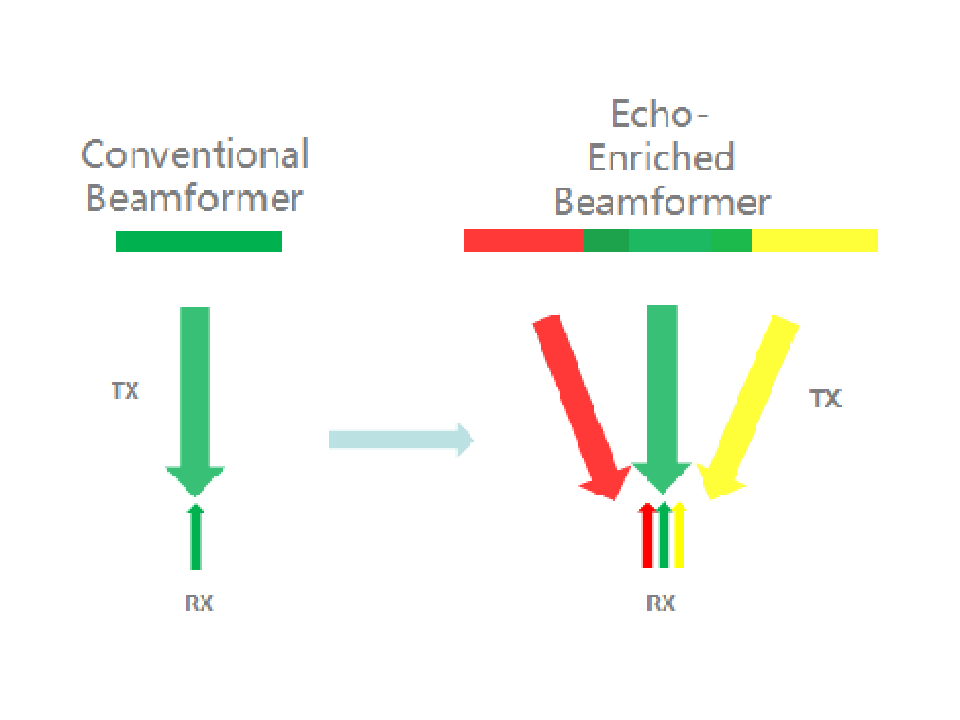

Based on Mindray's new generation ultrasound platform, mQuadro, M9 has raised the industry standards to an all new level. Advanced signal transmission and reception processors provide highly sensitive and accurate echo detection. Innovative transducer technologies allow for better penetration, higher resolution, greatly enhancing your diagnostic experience.